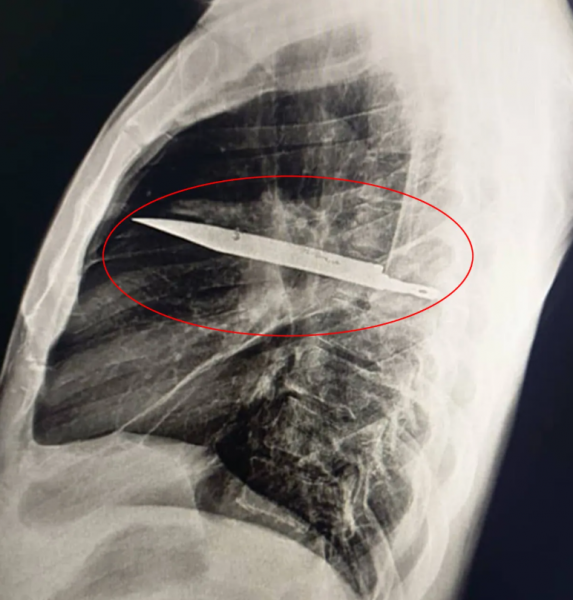

Недавно 44-летний мужчина обратился в медучреждение с жалобами на боль и гнойные выделения из правого соска. Врачи провели ему рентген-исследование и были ошеломлены. Оказалось, что в груди пациента застряло длинное лезвие ножа. Узнав об этом, мужчина вспомнил, что восемь лет назад в ходе ссоры получил несколько ножевых ранений, после чего прошел лечение и считал, что все зажило.

Однако нож, вошедший внутрь через правую лопатку, так и остался внутри и лишь чудом не повредил жизненно важные органы. Гной, который появлялся недавно, образовался из-за омертвевших тканей вокруг лезвия. Операция по извлечению инородного тела прошла успешно. Мужчина провел сутки в реанимации, а затем еще 10 дней в общей палате. Восстановление прошло без осложнений.